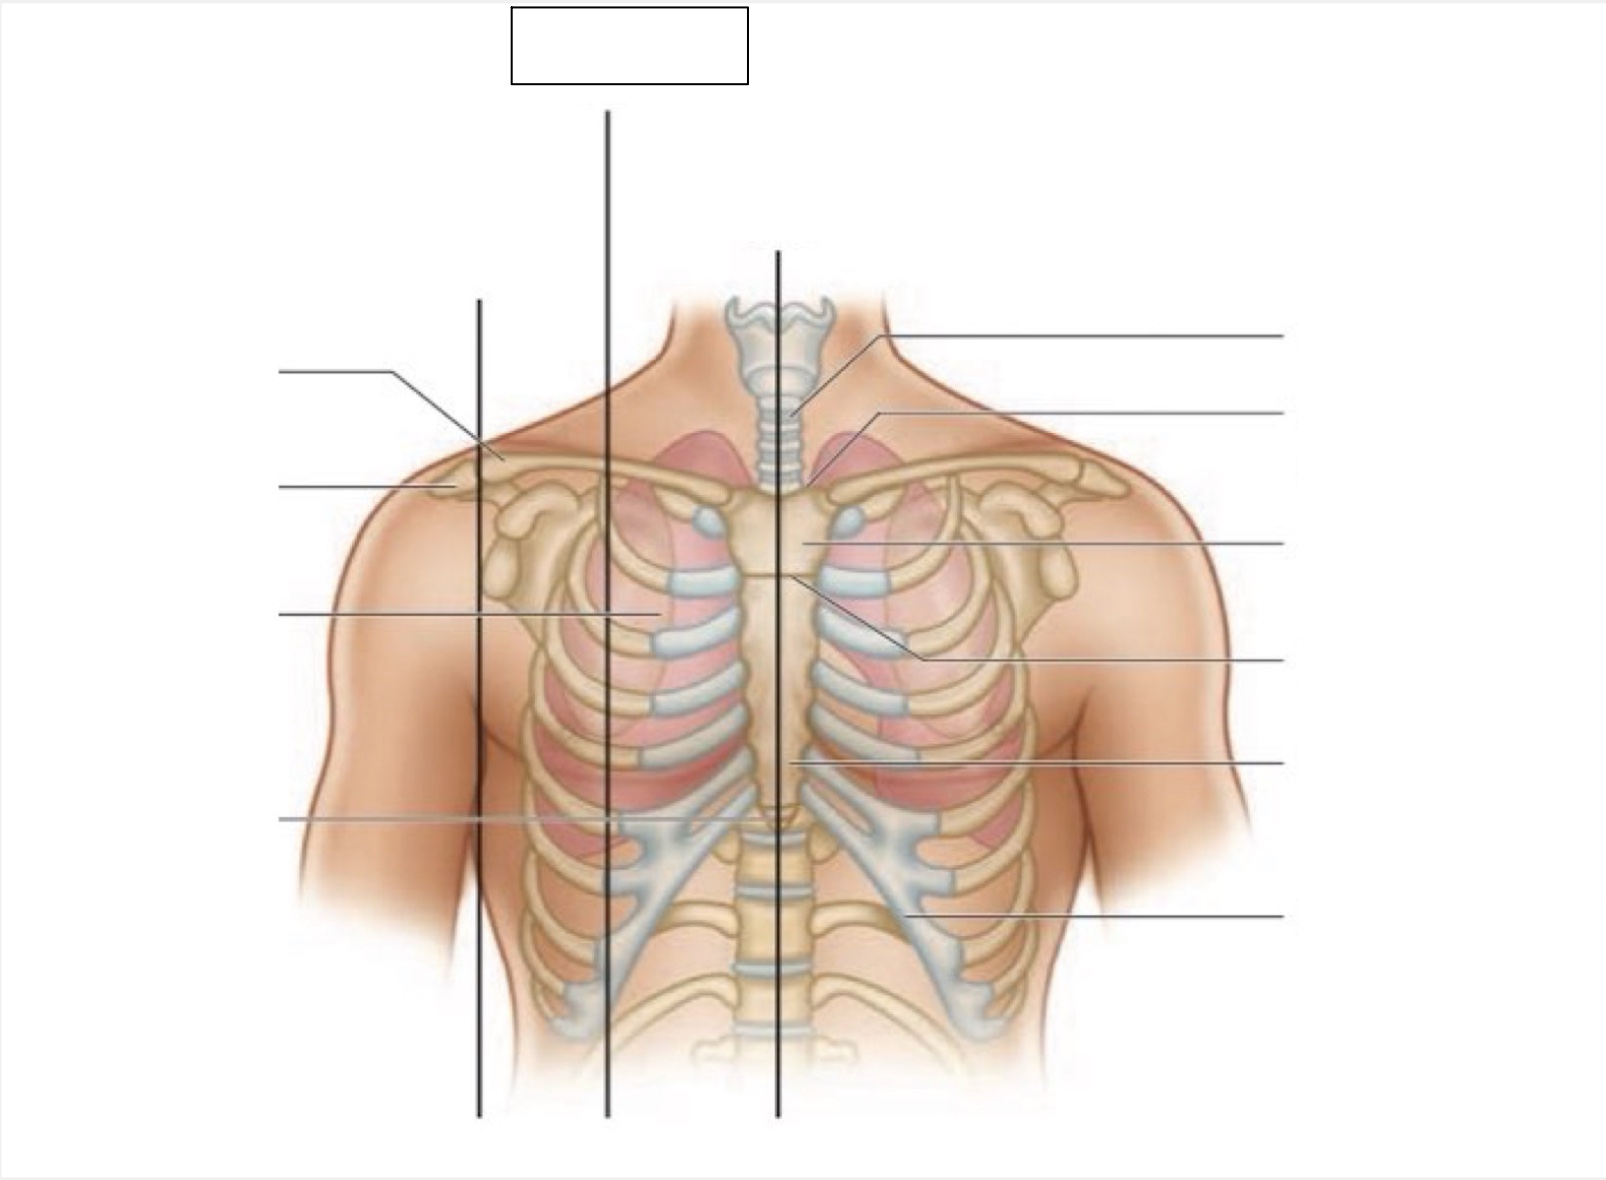

midsternal line

trachea

suprasternal notch

manubrium

angle of Louis

sternum

costal margin

xiphoid process

intercostal space

acromion

clavicle

anterior axillary line

midclavicular line